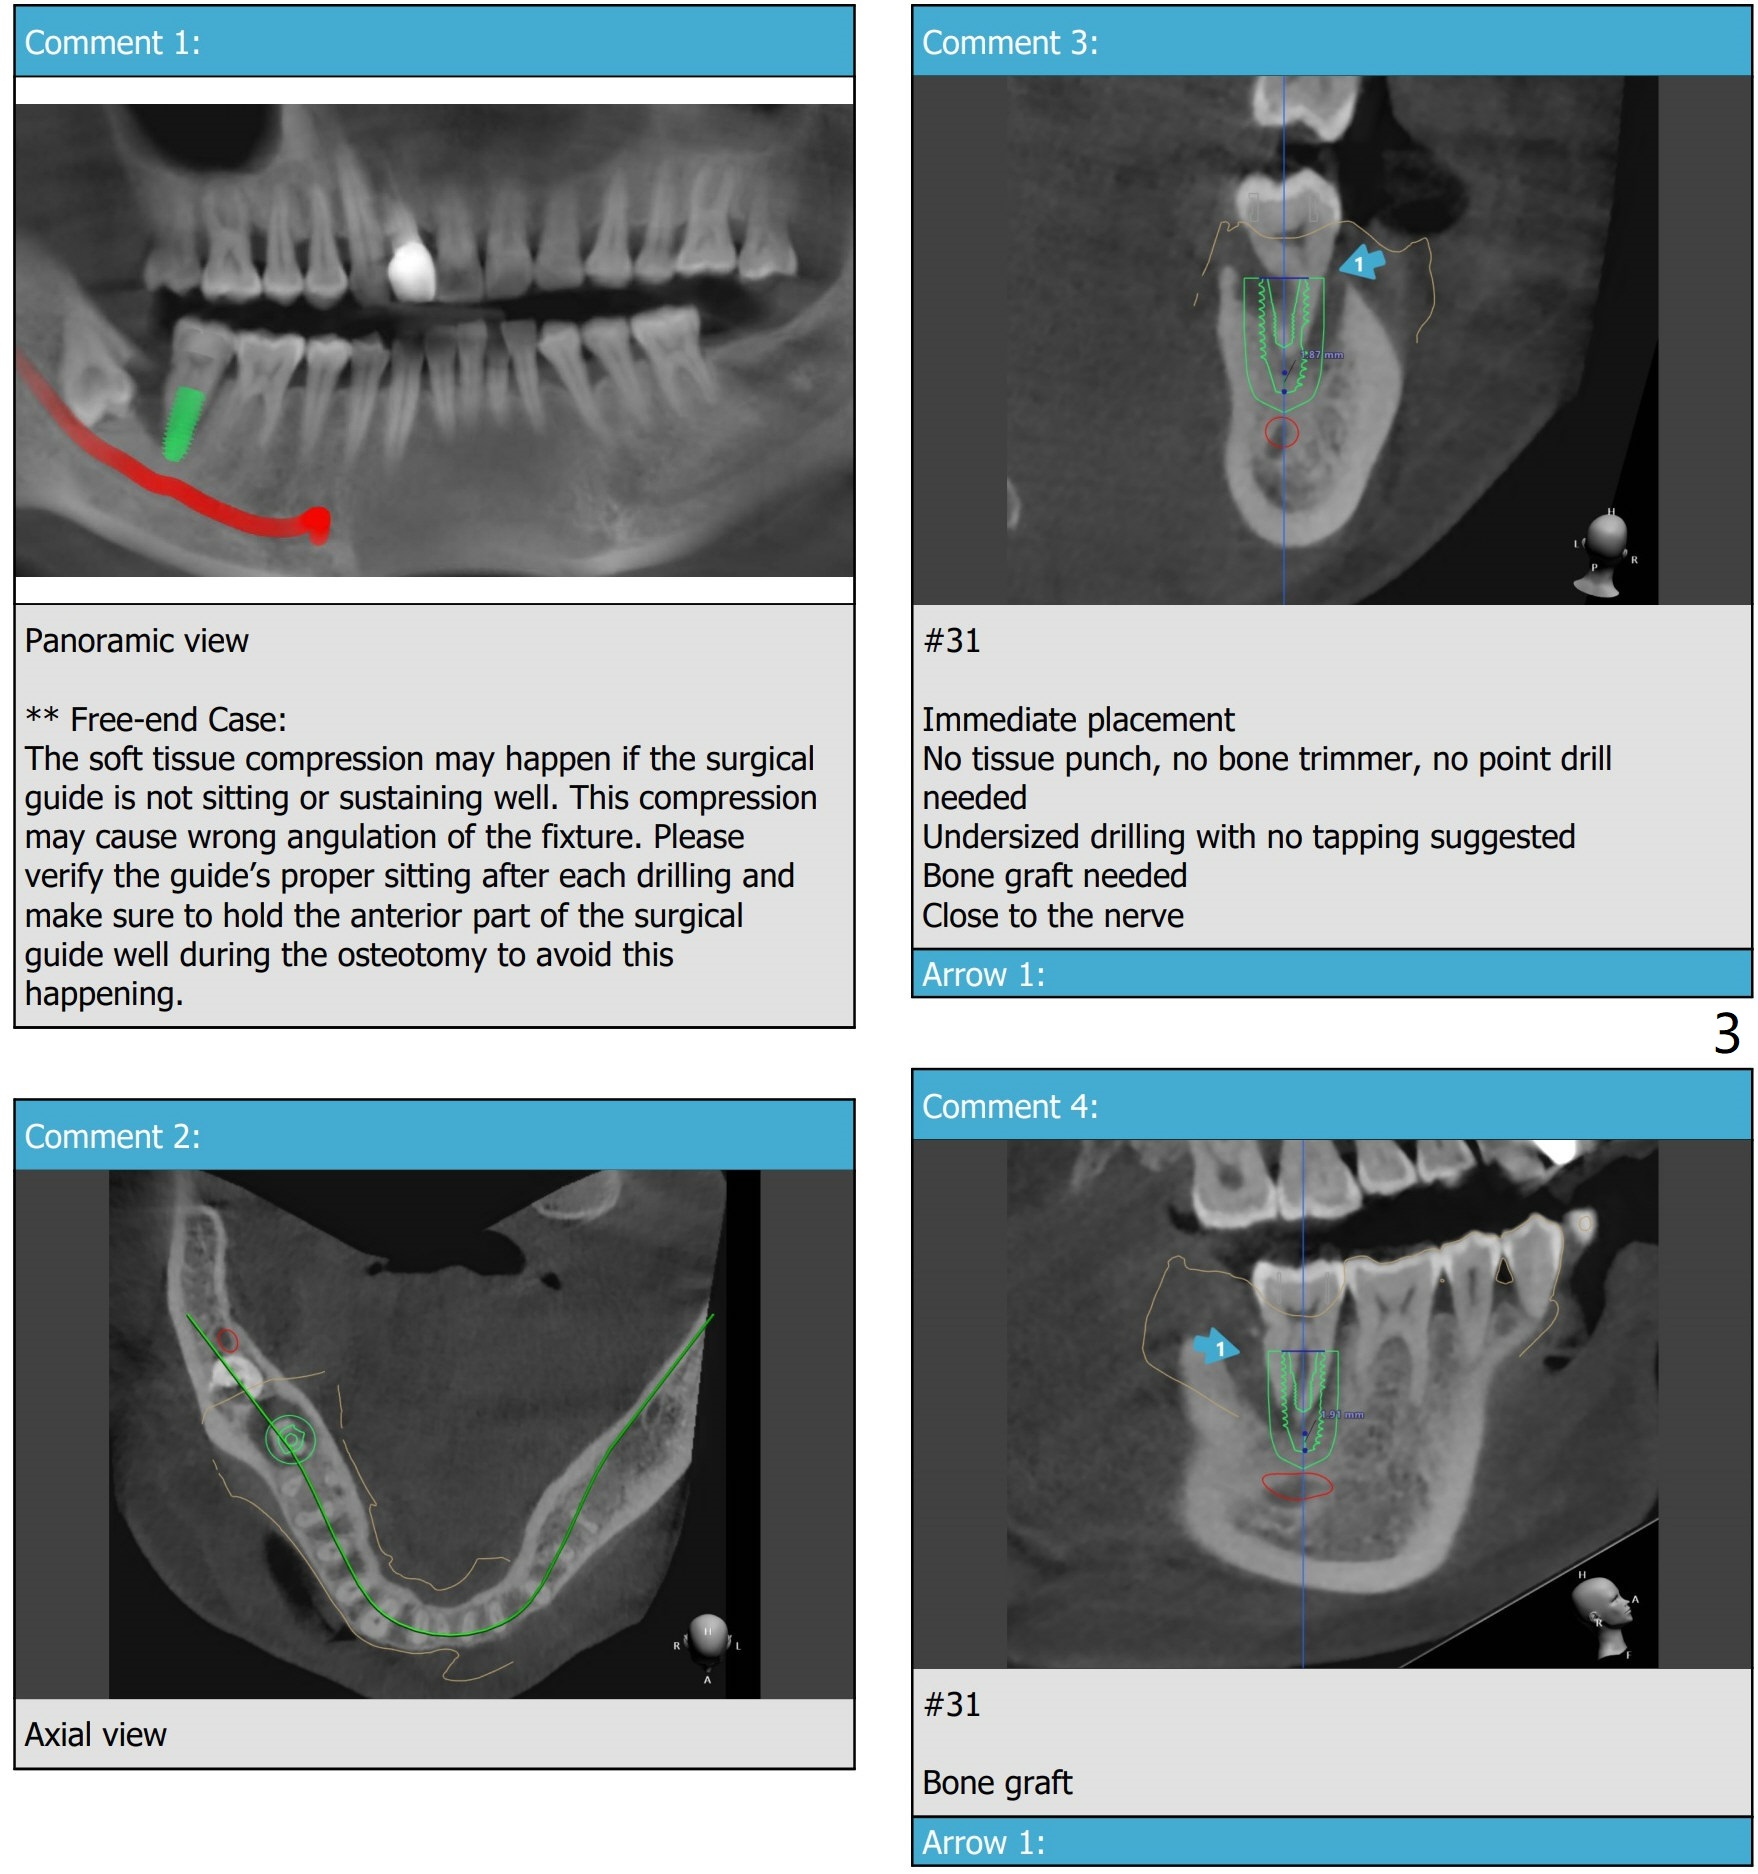

PRFx2/3,2 types of sticky bone: cortical (3/4) + synthetic bone (1/4) for #32; cortical (100%) for #31. Sequence: ext 31, implant, incision (if there is time), ext 32, bone graft. Place tatum implant 5x14 mm after 4.5 and 5.0x14 mm taps. Insert 4x3 mm Unipost, prepare margin, temp, perio dressing